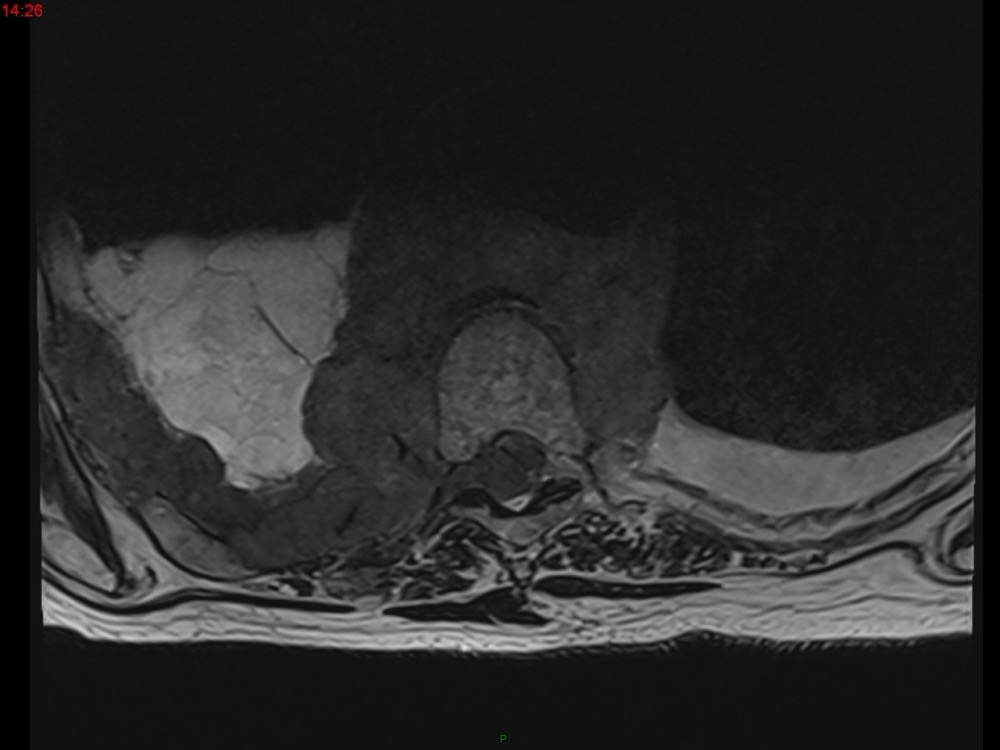

Marie Pauline Talabard 11/01/2023